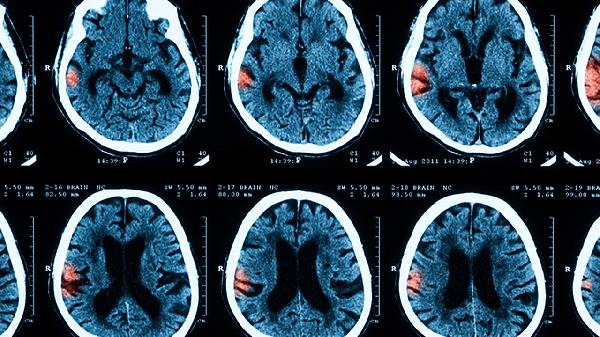

四个月大宝宝出现这些症状要警惕脑膜炎

四个月大的婴儿如果患上脑膜炎,早期可能会出现发烧、不愿意吃奶、精神萎靡等症状。随着病情发展,可能会出现前囟门鼓胀、频繁呕吐、抽搐等情况,严重时甚至会出现身体僵硬或昏迷。脑膜炎的诱因可能包括B族链球菌感染、大肠杆菌感染、肺炎球菌感染、单纯疱疹病毒感染,或者是新生儿败血症等,一旦发现应尽快送医治疗。